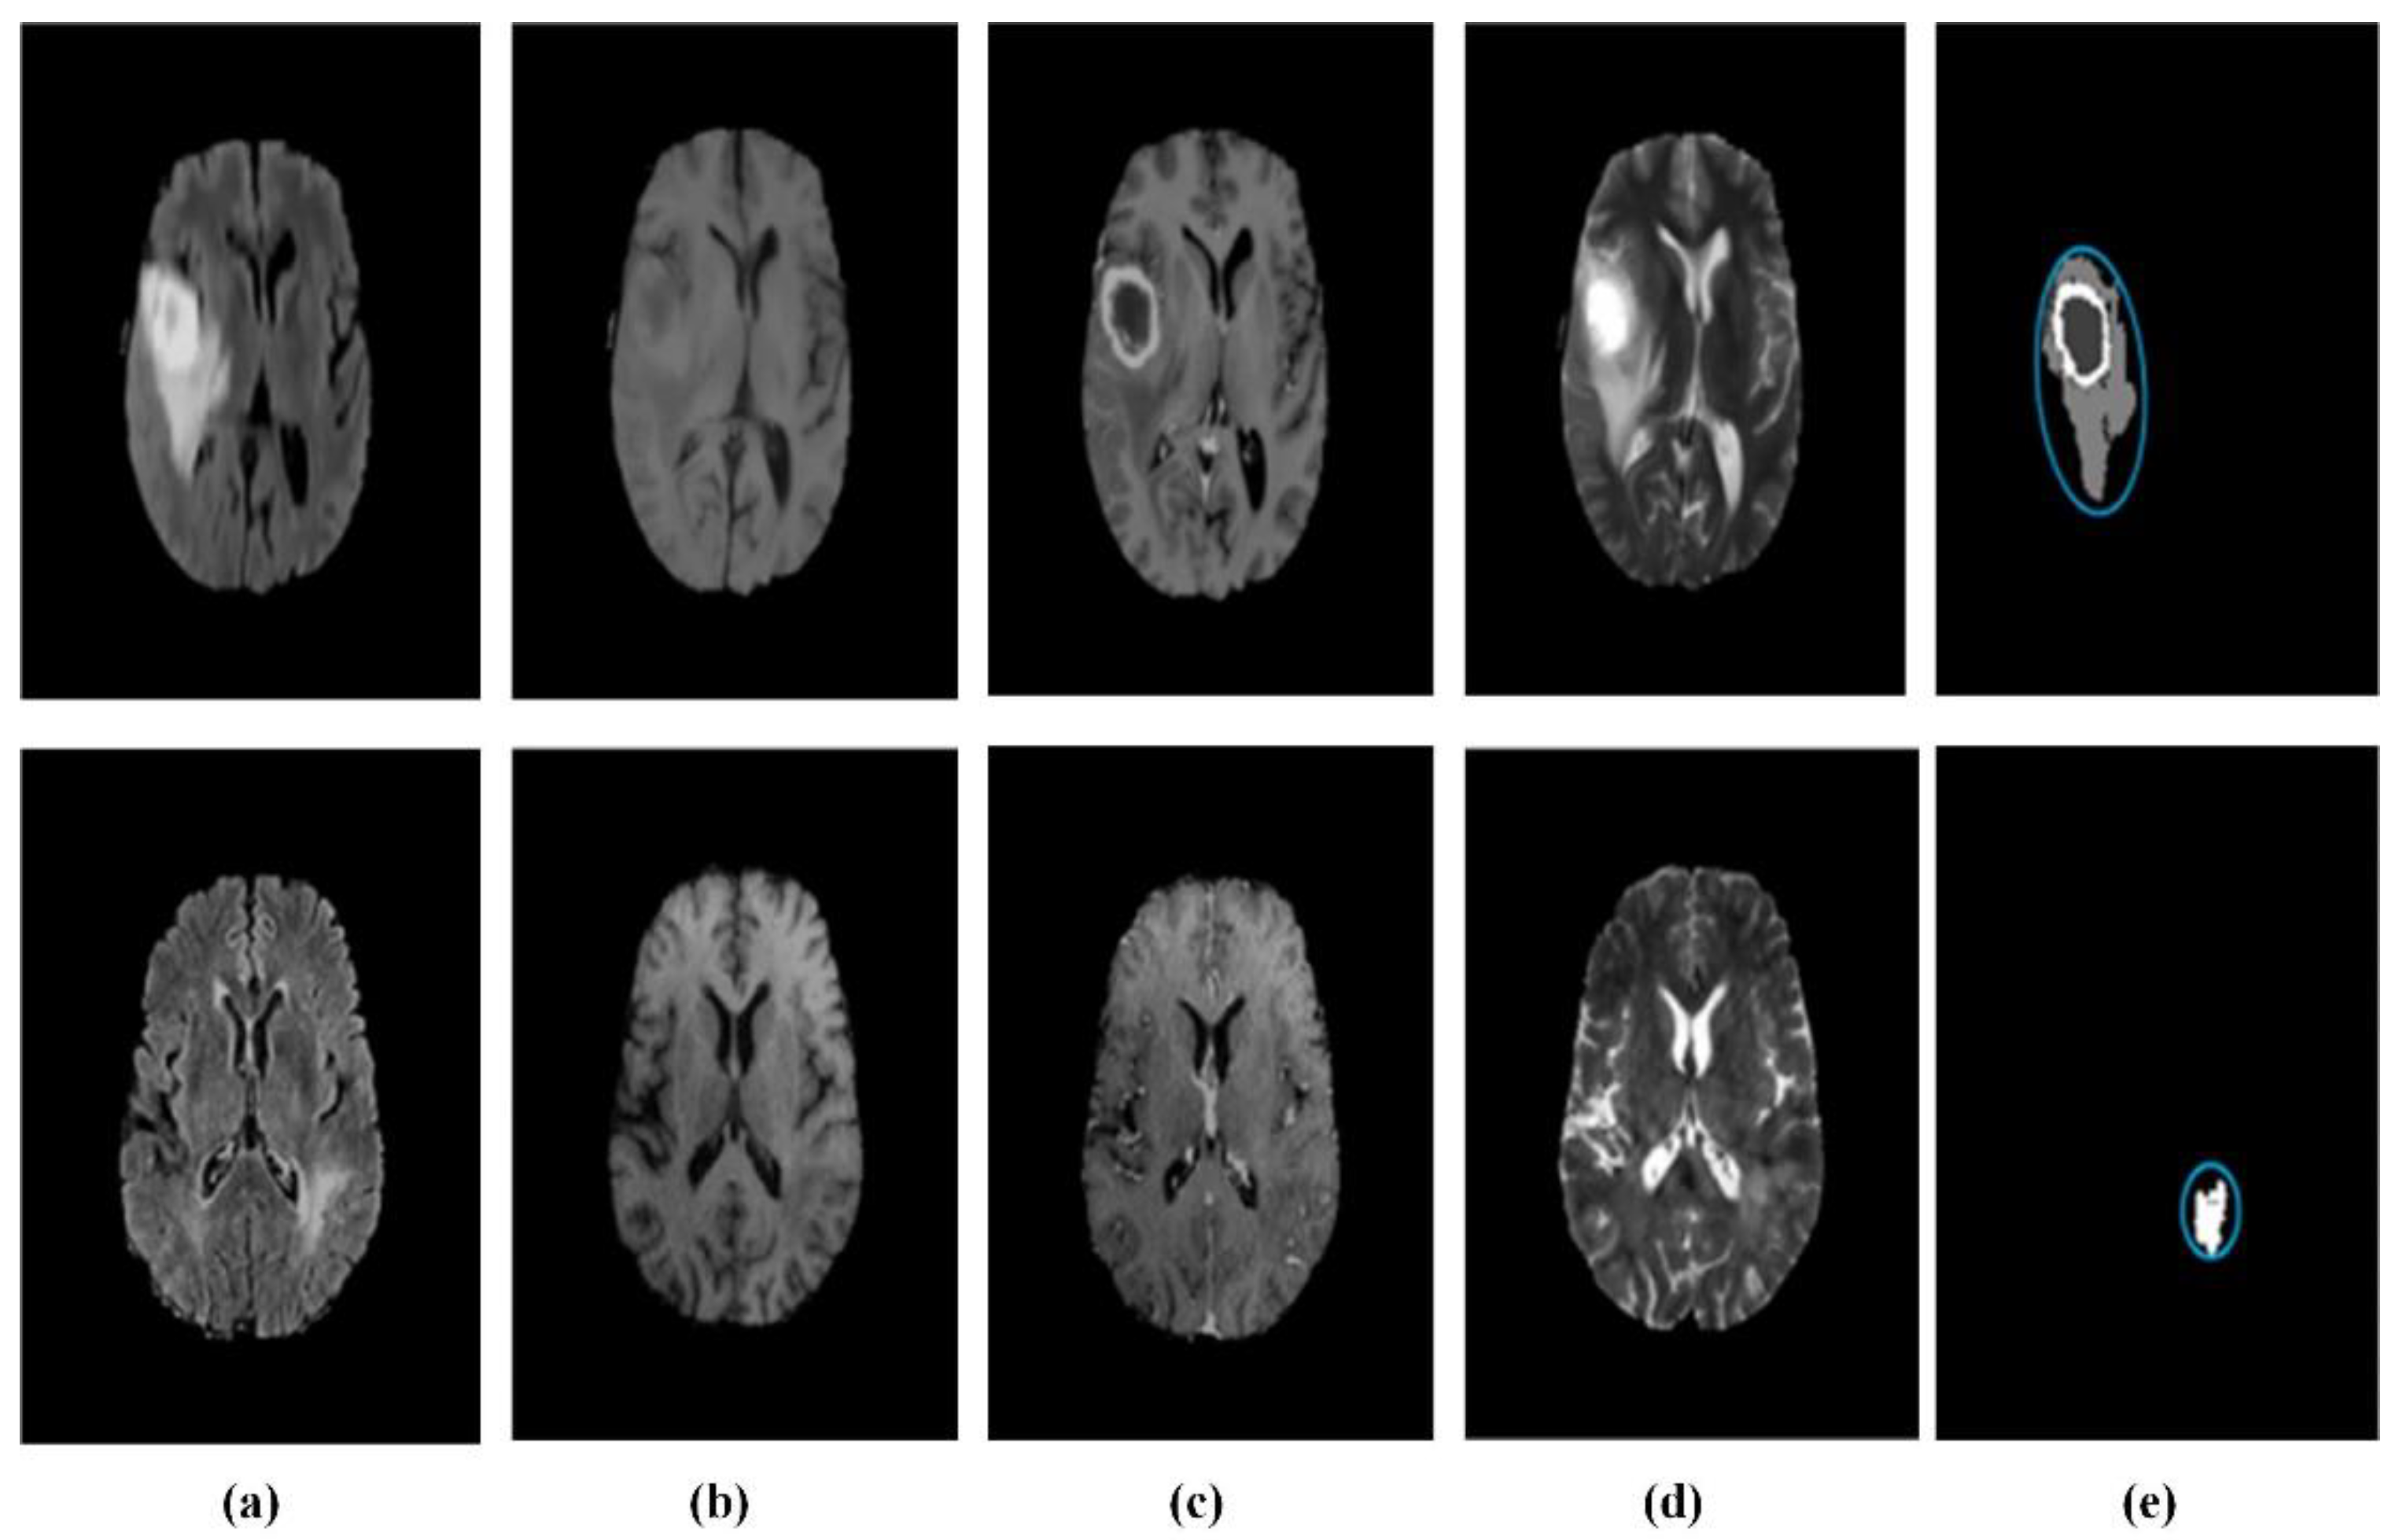

4.3. Application of Machine Learning in MRI Brain Tumor Segmentation Image